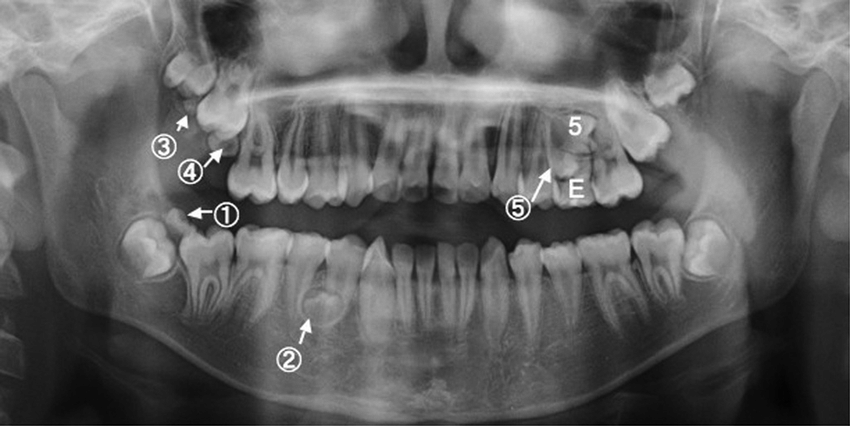

La radiographie panoramique dentaire est un examen d’imagerie permettant d’obtenir une vue d’ensemble des dents, des mâchoires, des articulations temporo-mandibulaires et des sinus maxillaires.

• Dents incluses ou surnuméraires

• Suivi orthodontique